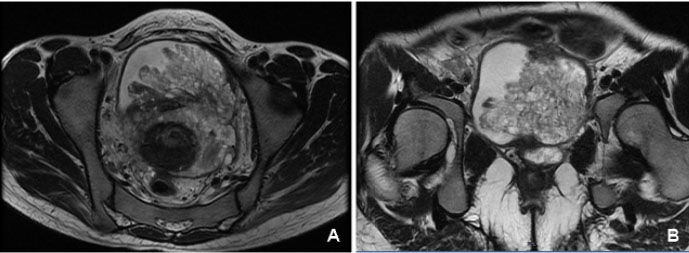

The Doppler ultrasound scan performed 2 weeks after the initial review described the right testicle as appearing diffusely hypoechoic with no presence of internal vasculature. The right scrotum also had a collection with internal septum suggestive of an infected hematoma (Figure 1). The left testis and epididymis had normal echotexture and vasculature. The ultrasound scan therefore showed radiological features of an avascular right sided testicle (Figure 2).

Figure 1: Ultrasound scan of the right testicle showing internal septum suggestive of an infected hematoma.

Figure 2: Doppler ultrasound scan of the right testicle showing no internal vasculature.

However, when diagnosing scrotal pathologies especially after a surgery, physical examination, although important, is not completely reliable. The most effective way of ruling out other scrotal and testicular differential diagnoses would be with an ultrasound scan [5]. As in this case, the scan confirmed an infected scrotal hematoma but also showed an avascular testicle.